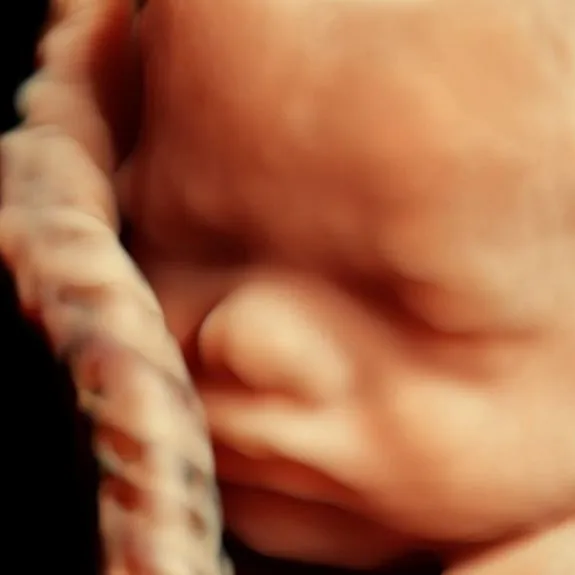

d) Ultrasound 5D [PROMOSI HARI RAYA RM149]

Teknik : Ultrasound dilakukan dengan menggunakan probe khas yang dilalukan ke atas bahagian kulit abdomen untuk melihat bayi secara ‘live’.

Jenis ultrasound :

1. 4D : Gambar dan video berwarna kuning keemasan.

2. 5D : Gambar dan video berwarna yang lebih realistic dan hampir menyerupai warna kulit.

Usia kandungan : 24-32 minggu

Tujuan pemeriksaan :

- Melihat bentuk wajah bayi

- Melihat pergerakan bayi secara ‘live’

- Mengenalpasti kecacatan luaran seperti sumbing atau kecacatan anggota (dalam limitasi tertentu).